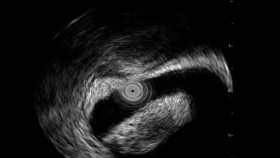

消化内科在消化内镜技术、功能性胃肠病、胰腺疾病、消化道肿瘤、肝脏疾病等各种常见胃肠道疾病诊断和治疗方面具备丰富的经验,尤其是在各种消化系统少见病、疑难病的诊治以及各种危重病例的综合抢救方面达到一定水平。消化内镜诊疗中心配备Pentax高清系列胃镜、肠镜,以及超声内镜,已经开展了国内外绝大多数内镜及介入治疗技术,如:胃肠道早期肿瘤的内镜下肿瘤剥离术,胃肠道息肉内镜下EMR术、食道扩张支架、贲门失迟缓POEM、ERCP、EST、内镜下胆道疾病治疗系列技术(胆道扩张、胆道支架等)、食道静脉曲张硬化套扎术、胃底静脉曲张硬化剂注射、双气囊小肠镜检查等,并结合多种新型内镜技术确定早期胃癌诊断标准及开展内镜下微创治疗。